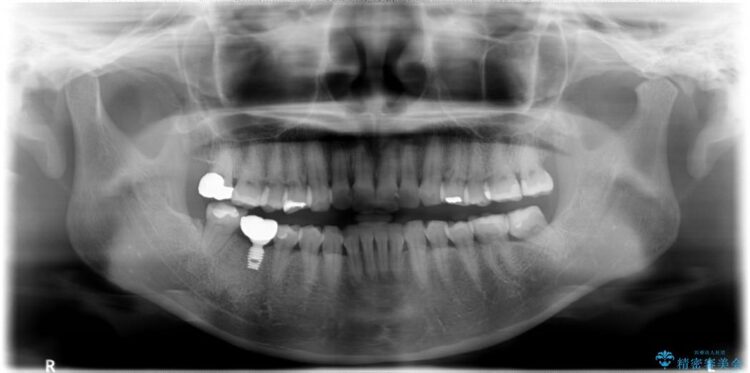

【30代女性】右下奥歯のインプラント 治療例

- 患者様:30代女性

- 治療期間:6ヶ月

- 概算治療費:35万円

他院で右下の奥歯を抜歯しなければならないと言われ、当院へ相談に来られました。

精密な検査を行ったところ、根が完全に折れている為、抜歯が必要となりました。抜歯後は骨と歯茎が痩せてしまう事がないように、人工の骨をつめ、インプラント治療を行う計画としました。